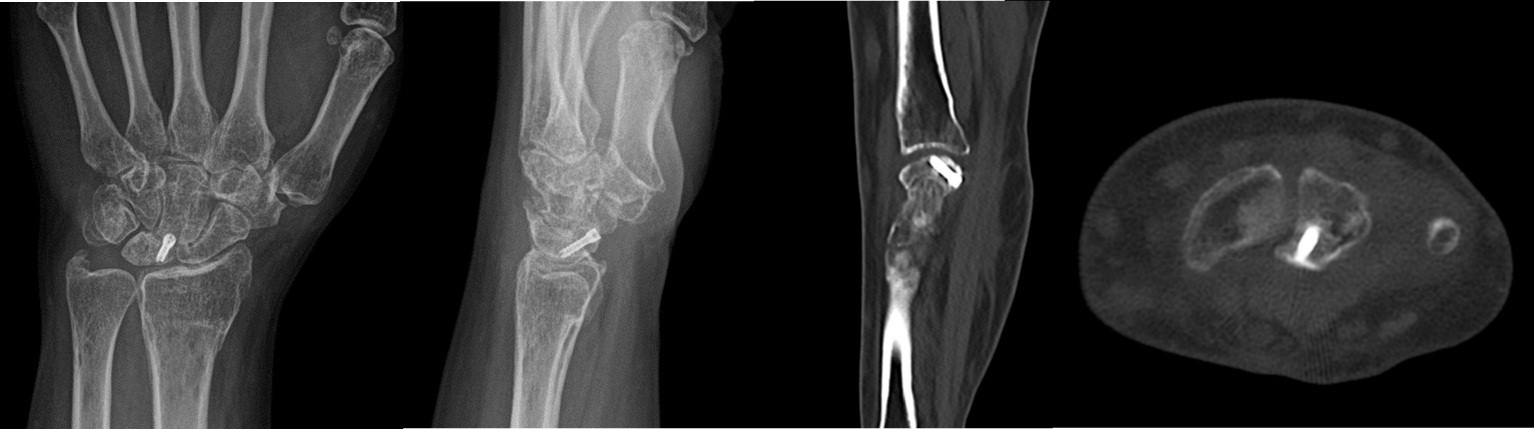

- Patient B: A 47-year-old left-handed housewife presented with a 1-year history of left wrist pain. She reported no history of trauma, was a non-smoker, and had no significant medical history (Fig. 4, 5, 6).

Figure 4: X-ray radiographic ulnar index of −3.7 mm.

Figure 5: Computed tomography scan.

Figure 6: Magnetic resonance imaging.